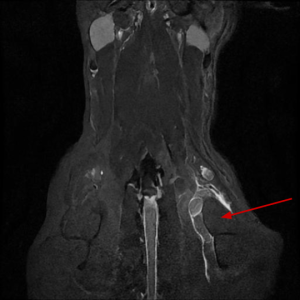

Main Gallery

Playing with a photo gallery function. It is possible to have multiple galleries, each within a namespace.